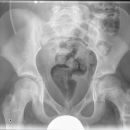

Shuntverlauf

Shuntkontrolle

1. Schädel/HWS ap

Patient in Rückenlage, Kinn anziehen lassen, 15° Keil unter den Kopf, so dass Deutsche Horizontale (DH = Frankfurter) senkrecht zum Film steht, Kopf muss seitengleich, symmetrisch gelagert werden.

2. Schädel/HWS seitlich

Patient in Rückenlage, Kopf auf die rechte Seite drehen und Medianebene verläuft parallel zum Tisch, Stirn-Augenbrauen-Linie verläuft senkrecht und die Stirn-Kinn-Punkte verlaufen parallel zur Filmeinblendung. Der Körper dreht sich somit etwas auf die rechte Seite.

3. Thorax/Abdomen

Patient in Rückenlage, Arme am Körper entlang, Beine geschlossen.

4. evtl Becken

Patient in Rückenlage, Beine leicht gespreizt.

Senkrecht auf Objekt, vom Schädel bis Abdomen müssen alle Bilder überlappend sein.

Die Stelle (Narbe) an der der Shunt in dem Abdomen verschwindet, muss mit einer Metallkugel etc. markiert werden.